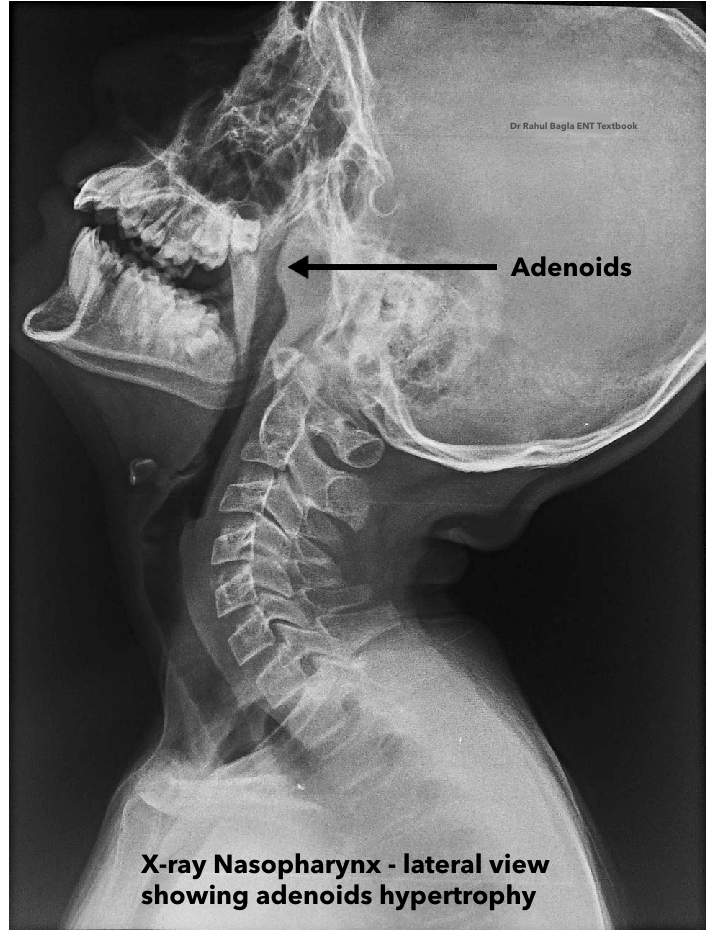

- Soft tissue lateral view radiograph of the nasopharynx: This is a valuable, non-invasive imaging modality. It can reveal the size of the adenoids and, more importantly, the extent of nasopharyngeal air space compromise.

Important for Viva: An examiner might ask you to differentiate between an enlarged adenoid and an antrochoanal (AC) polyp on a lateral radiograph. Remember this key distinction: in the case of an AC polyp, you will see a column of air present along the posterior and superior walls of the nasopharynx, which is absent with a true adenoid mass. This is because the AC polyp arises from the maxillary sinus and extends into the nasopharynx, leaving an air column around its pedicle.

- Soft tissue lateral view radiograph of the nasopharynx: This is a valuable, non-invasive imaging modality. It can reveal the size of the adenoids and, more importantly, the extent of nasopharyngeal air space compromise.

- Radiological View: Lateral soft tissue view of nasopharynx.